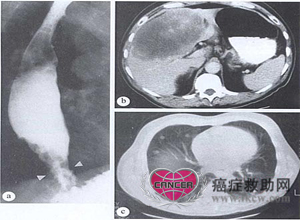

腺癌。59岁男性患者,体重下降,伴上腹部疼痛及轻度吞咽困难。食管镜检查,见食管下1/3段的缩窄性病变。(a)钡餐显像展示病变范围(箭头)。CT扫描显示(b)肝脏大转移灶,以及(c)肺早期转移灶。